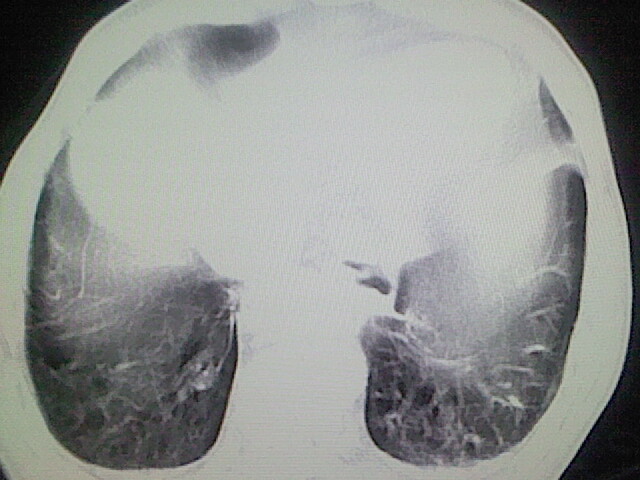

以下是引用zsl6918在2008-8-28 16:49:00的发言:[br]双肺炎性病灶,食管狭窄估计与心房增大压迫所致。

以下是引用xulianj在2008-8-28 20:36:00的发言:[br]慢支肺气肿伴感染,右上肺陈旧性结核;食道建议胃镜检查。

以下是引用wqs571018在2008-8-28 21:18:00的发言:[br]慢支继发感染,右上肺陈旧性结核;食道建议胃镜检查。